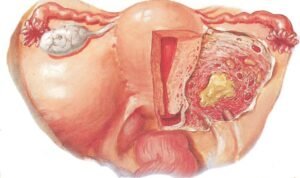

PID can be defined as infection of the upper genital tract involving the cervix (mouth of the uterus), uterus, fallopian tubes, parametria (sides of the uterus and ovaries).